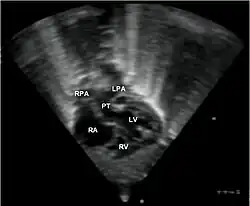

- Echocardiogram: An echocardiogram is an ultrasound of the heart that accurately assesses the heart’s structure and function, and can show the specific features of TGA, if present. This imaging modality allows for the definitive diagnosis of TGA to be made.[3]

Abbreviations: RA=right atrium, RV=right ventricle, LV=left ventricle, PT=pulmonary trunk, LPA and RPA=left and right pulmonary artery.